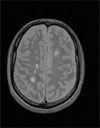

Το φυλλικό οξύ προστατεύει από το αιμορραγικό εγκεφαλικό επεισόδιο

Νέα Υόρκη: Εκτός από την επίδρασή του στην ομοκυστεΐνη, ένα αμινοξύ που σχετίζεται με τα καρδιακά νοσήματα, το φυλλικό οξύ, προστατεύει τον οργανισμό από το αιμορραγικό εγκεφαλικό επεισόδιο, σύμφωνα με σουηδική μελέτη που δημοσιεύεται στο επιστημονικό έντυπο Stroke.